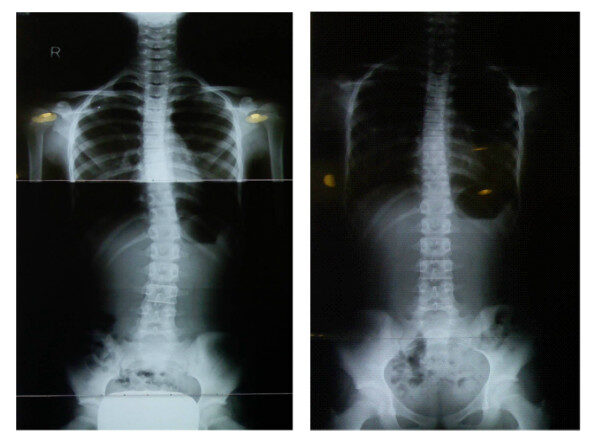

척추측만증이 의심된다면 근처 정형외과에서 X-RAY촬영을 통한 척추측만증의 발병여부를 파악하고, 어떤 방법으로 치료 하는지가 가장 중요하다. 특히 16세가 되기 전에 척추측만증 진단을 받은경우, 성인이 되면 휘어짐의 각도가 점점 더 커질 수 있어 조기치료가 필수적이다.

인본병원 척추센터 송형석 원장은 “척추측만증은 정확한 진단과 치료를 받을 수 있는 병원에 내원하는 것이 좋으며, 방치하면 악화될 확률이 높아 X-RAY검사 후 조기치료가 중요하다”라고 조언했다.